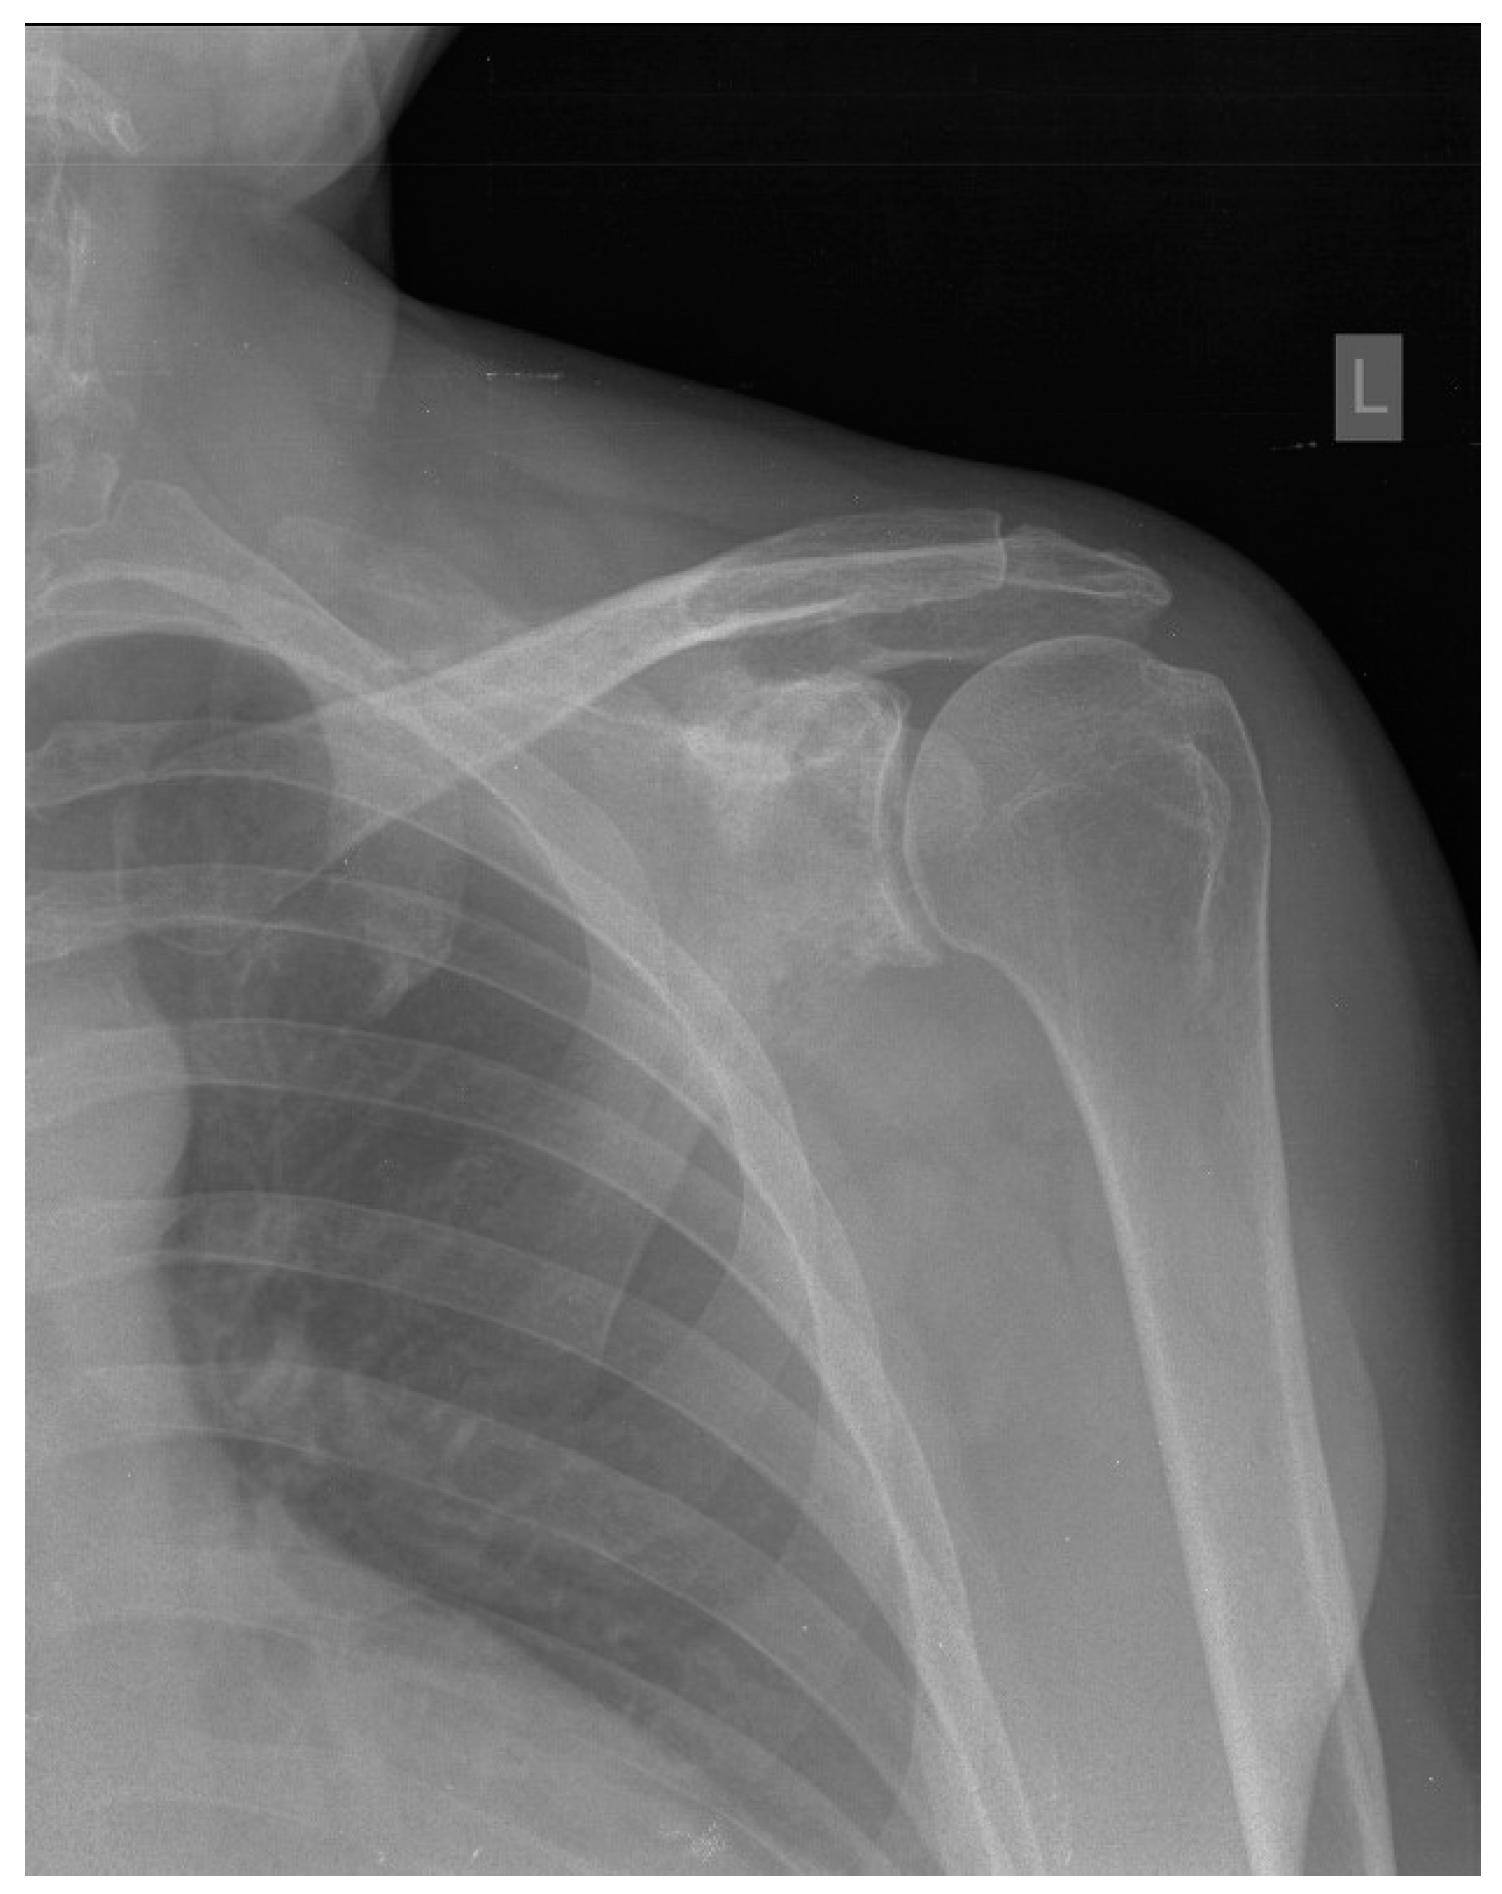

2. Case Report

| Our patient | M/45 y | Paresthesia, tingling, numbness and edema of the little and ring fingers | Two years/ two years | Surrounding soft tissue | R-CHOP chemotherapy + radiotherapy | Remission |